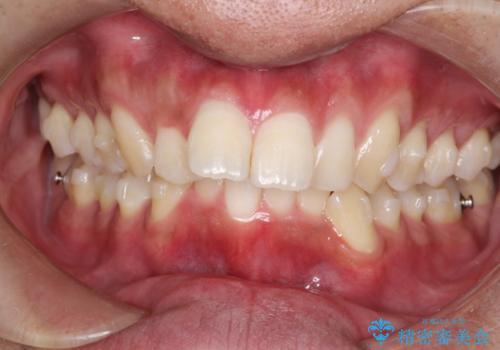

インビザラインによる出っ歯の矯正

- 出っ歯と下の歯のガタガタを主訴に来院されました。

上の奥歯を後方に移動させて、スペースを作り前歯を内側に引っ込める計画としました。

インビザラインによるマウスピース矯正で治療をすることとしました。

インビザラインをしっかり使用していただいたので、スムーズに治療をおえることができました。